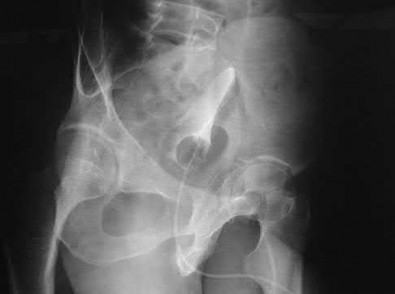

A 76-year-old male community ambulatory presented to clinic complaining of pain in the left groin that has been persistent for the last 8 months. Radiographs obtained from clinic are seen in Figure A. You suspect a femoral neck nonunion and obtain a CT scan which confirmed it. Which of the following statements is true?

A total hip arthroplasty (THA) after nonunion of a femoral neck fracture would provide the best long term outcomes in a 76-year-old male who is a community ambulator.

After nonunion of a femoral neck fracture, hemiarthroplasty and THA are good salvage option for the physiologically older patients. When deciding between these two options, THA is better for active and cognitively intact patients. THA is also indicated in patients with radiographic evidence of degenerative disease about the acetabulum. Hemiarthroplasty is advocated for patients who are older and less active.

Yang et al. retrospectively investigated the risk factors for nonunion in patients treated with cannulated screws. They reviewed 202 patients who had femoral neck fractures and were treated with internal fixation with cannulated screws. They identified that triangle configuration, displaced fracture, borderline or unacceptable reduction, and increased screw shaft subchondral purchase over the femoral neck were all risk factors for nonunion after internal fixation.

Inverted triangle configuration was found to increase rate of union.

Archibeck et al. retrospectively reviewed the outcomes of 102 THAs after failed internal fixation for a hip fracture (including both femoral neck and intertrochanteric). They concluded that the conversion of failed hip internal fixation has elevated risks compared to a primary THA, however, it may still be successful. The biggest concern for these patients postoperatively are periprosthetic fracture and dislocation.

Figures and Illustrations:

Figure A is an AP pelvic radiograph demonstrating a nonunion of a femoral neck fracture after suboptimal fixation with 3 cannulated screws in a triangle configuration.

Illustration A is an AP radiograph of the left hip in this patient following conversion to THA.

Illustration B is a radiograph demonstrating a valgus osteotomy. Illustration C shows an example of a femoral neck nonunion with varus malreduction.

Incorrect Answers:

Answer 2: Varus reduction is closely correlated with failure in this fixation method.

Answer 3: The patient's best outcome would be with THA.

Answer 4: This would be a good option in a younger patient, but given age and functional capacity, the best option is THA.

Answer 5: Patients with hemiarthroplasty have lower rates of dislocation.